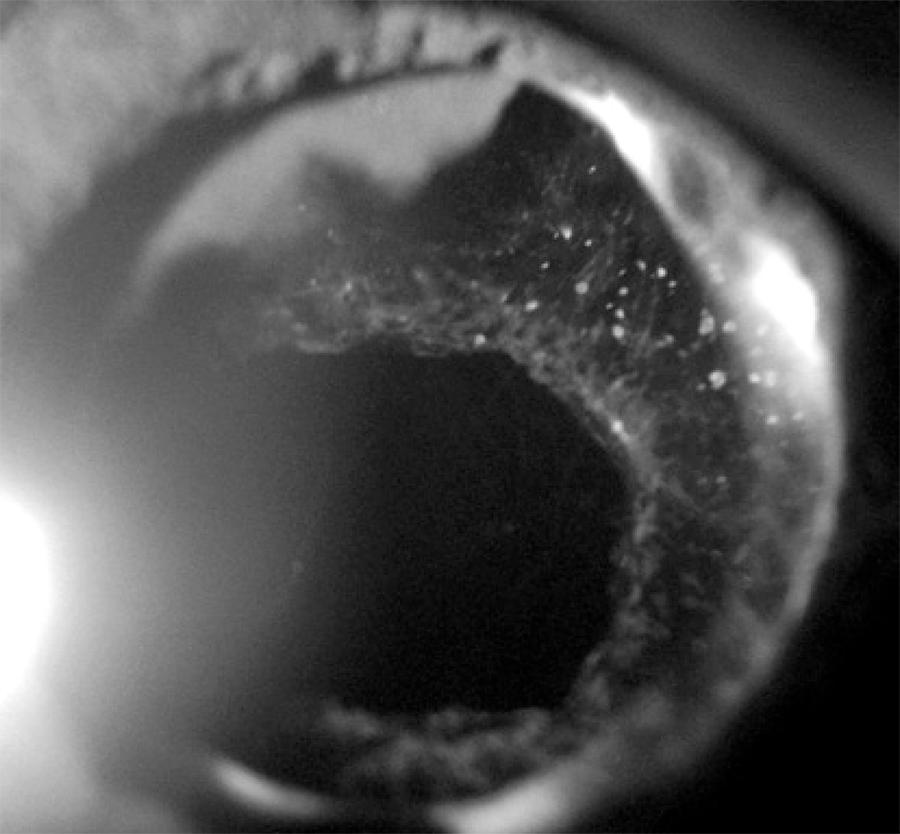

Four years after surgery, 39 out of 58 patients (67%) had PCO as detected by a slit lamp examination. Of the total, 24 eyes (41.3%) had decreased VA due to PCO and were referred for Nd:YAG laser capsulotomy (Figure 1). Three eyes (5.1%) had decreased VA due to glaucoma, IOL opacification, and age-related macular degeneration, respectively. In a further 12 eyes (20.7%) with mild PCO, VA remained unchanged.